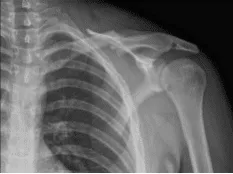

Se vio a un hombre de 20 años en la consulta quejándose de dolor en la clavícula izquierda. Sospechaba que el accidente de tráfico era la causa. El dolor le despierta del sueño. Puede ser muy doloroso y puede dificultar mover el brazo.

Se presentó una XR en la consulta y se encontró fractura clavicular en el centro del diástico con 1 cm de sobreposición y desplazamiento moderado. Las fracturas de la clavícula en la diáfise media son lesiones traumáticas frecuentes producidas por un impacto directo en la cintura escapular, y son más comunes en adultos jóvenes y activos.

Clavícula izquierda en posición AP